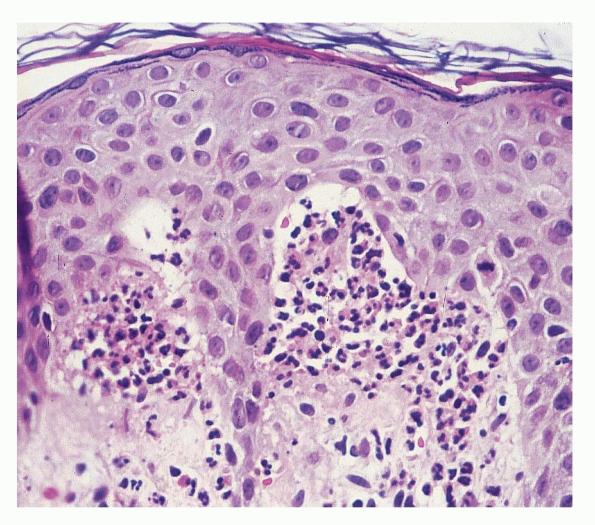

. The typical histologic features are best observed in erythematous skin adjacent to early blisters. In these zones, neutrophils accumulate at the tips of dermal papillae. With an increase in size to microabscesses, a significant admixture of eosinophils may be noted. As microabscesses form, a separation develops between the tips of the dermal papillae and the overlying epidermis; thus, the early blisters are multiloculated . The presence of fibrin in the papillae may give them a bluish appearance. Within 1 to 2 days, the rete ridges lose their attachment to the dermis, and the blisters then become unilocular  and clinically apparent. At this time, the characteristic papillary microabscesses may be observed at the blister periphery. For this reason, the inclusion of perivesicular skin in the biopsy specimen is of

utmost value. The papillary dermis beneath the papillae may have a relatively intense inflammatory infiltrate of neutrophils and some eosinophils. Many neutrophils may exhibit leukocytoclasis. Subjacent to this, a perivascular infiltrate composed of lymphocytes, neutrophils, and eosinophils may be apparent. the diagnostic finding of papillary microabscesses may not be present in all patients. Apoptotic keratinocytes may be noted above the papillary microabscesses.